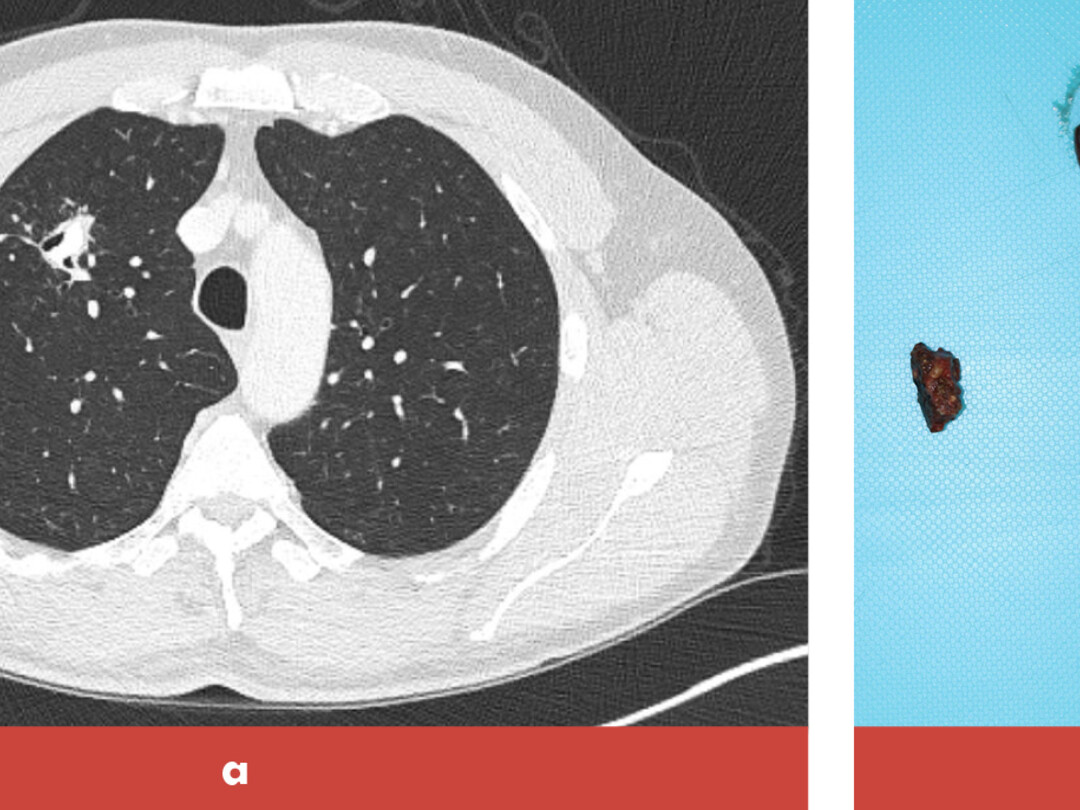

Een 43-jarige Servische man kwam op de polikliniek Longziekten in verband met episoden van enkele weken waarin hij kleine hoeveelheden bloed ophoestte, steeds in combinatie met het beeld van een luchtweginfectie. Een week voordat hij op de polikliniek kwam, had hij een orchidectomie ondergaan in verband met een testiscarcinoom. Een belangrijk detail uit zijn voorgeschiedenis was dat hij 25 jaar geleden in Servië een bomexplosie had meegemaakt, waarna hij meerdere operaties had ondergaan om bomscherven uit zijn huid te verwijderen. Bij auscultatie van de longen werd er vesiculair ademgeruis gehoord, zonder bijgeluiden. Een CT-thorax met contrast liet een caviterende…